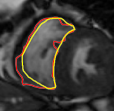

The problem above is a generalization of Horn & Schunck optical flow. Note that solving for the Horn & Schunck optical flow within each region separately does not lead to motions such that at the interface, they have equal normal components (see Figure 1), whereas the solution of (5) to be presented in subsequent sections does. Note that computing Horn & Schunck optical flow in each region requires boundary conditions (and typically they are chosen to be Neumann boundary conditions: and on ). Note that replacing these boundary conditions with the boundary constraint (6) does not specify a unique solution. Also, while Horn & Schunck optical flow computed on the whole domain naturally gives a globally smooth motion, which by default satisfies matching normals at the interface, this is not natural for the ventricles / myocardium, where different motions exist in the regions (see Figure 2), and the motions should not be smoothed across the regions.

![]() |

| image + boundary | global optical flow | our method | our method (motion decomp.) |